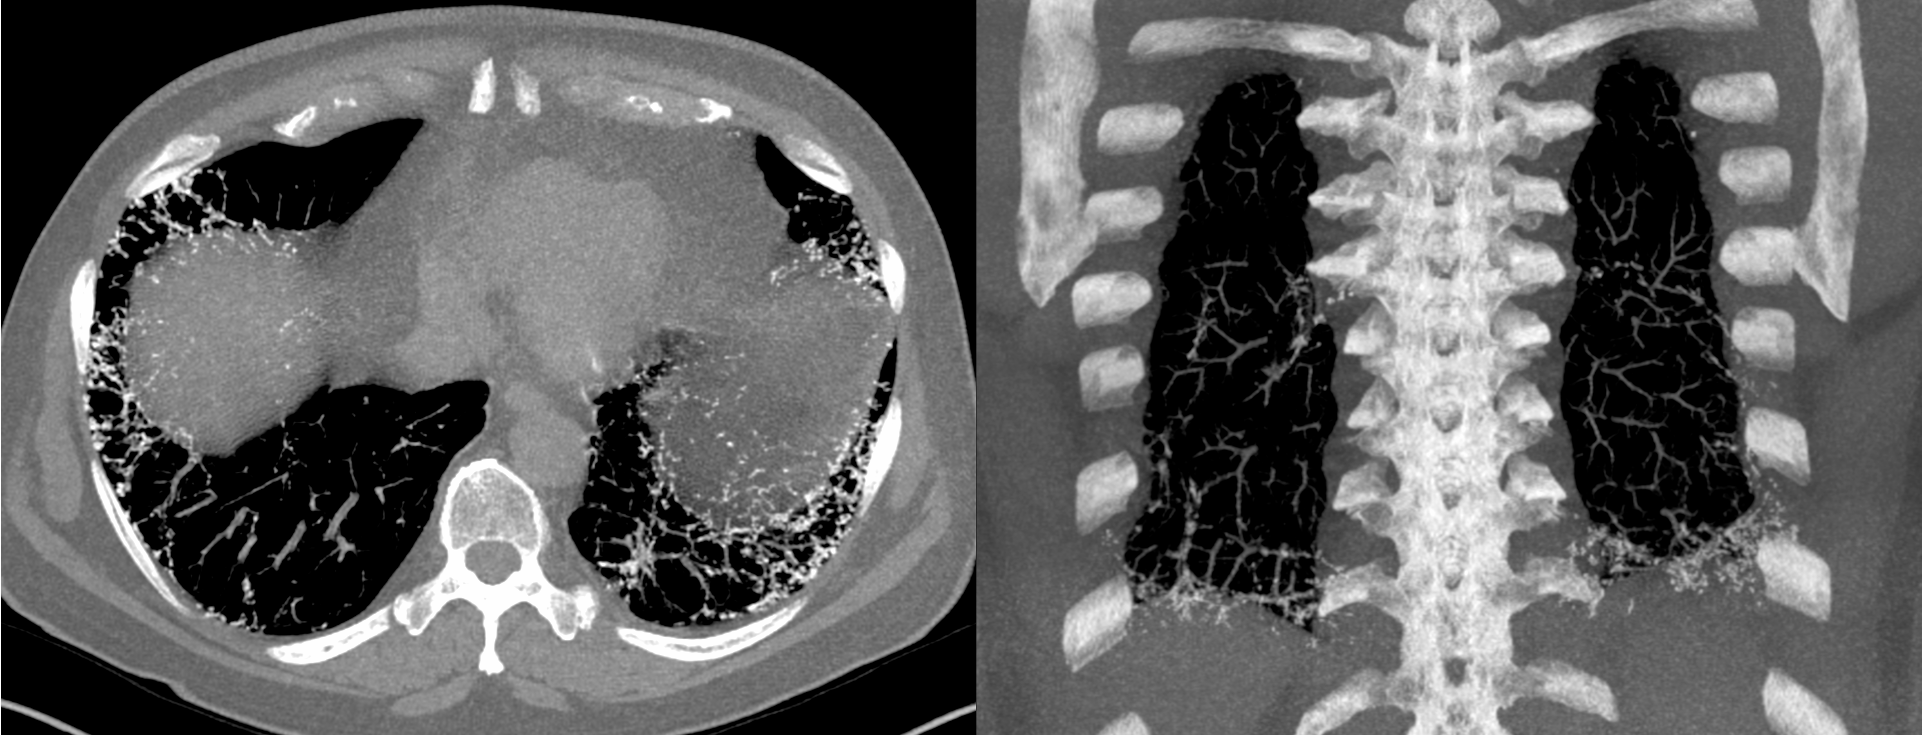

63-years old with a remote 4 pack years history of smoking came with mild dyspnea, and cough with expectoration

20 mm MIPs showed the classic lacy pattern of dendriform diffuse pulmonary ossification (DPO)